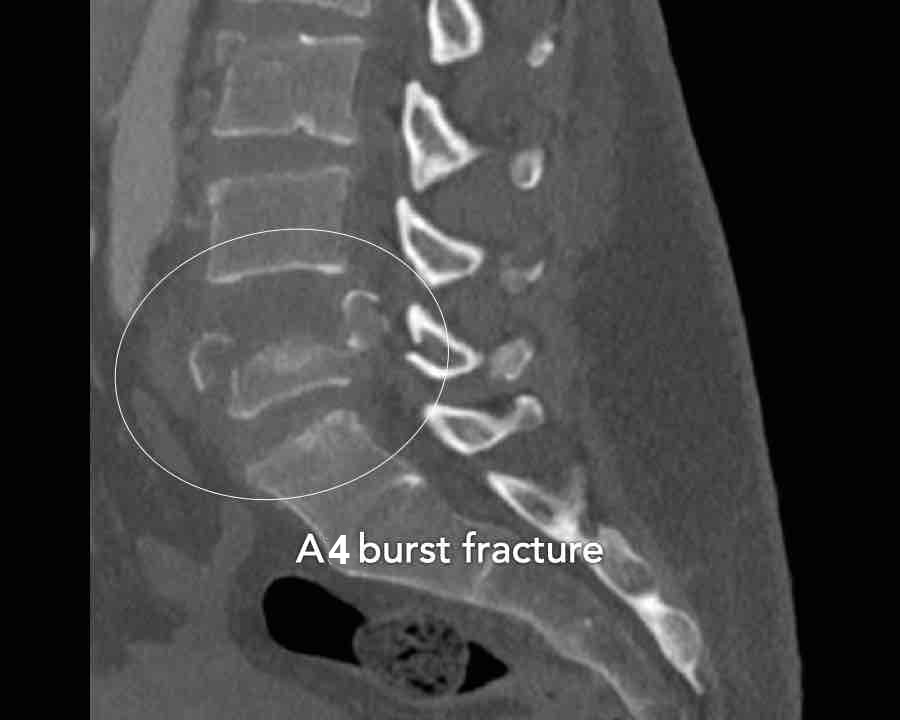

Findings

- The most severe level is L4/5 with dislocation (dotted lines)

- Facet fractures at L4 (arrows).

- A4 burst fracture (circle).

Conclusion:

Injury type C + A4 at L4/5.